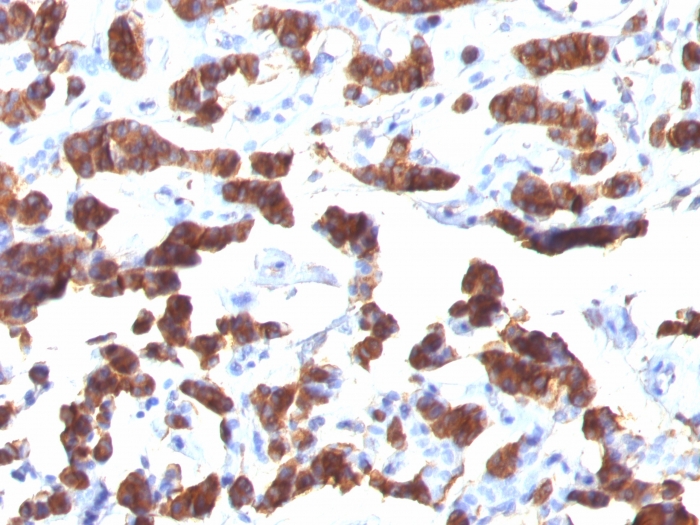

Thyroglobulin is a 660kDa dimeric pre-protein with multiple glycosylation sites. It is produced by and processed within the thyroid gland to produce the hormone thyroxine and triiodothyronine. Prior to forming dimers, thyroglobulin monomers undergo conformational maturation in the endoplasmic reticulation. The vast majority of follicular carcinomas of the thyroid will give positive immunoreactivity for anti-thyroglobulin even though sometimes only focally. Poorly differentiated carcinomas of the thyroid are frequently anti-thyroglobulin negative. Adenocarcinomas of other-than-thyroid origin do not react with this antibody. This antibody is useful in identification of thyroid carcinoma of the papillary and follicular types. Presence of thyroglobulin in metastatic lesions establishes the thyroid origin of tumor. Anti-thyroglobulin, combined with anti-calcitonin, can identify medullary carcinomas of the thyroid. Furthermore, anti-thyroglobulin, combined with anti-TTF1, can be a reliable marker to differentiate between primary thyroid and lung neoplasms.

Positive Control

Thyroid.